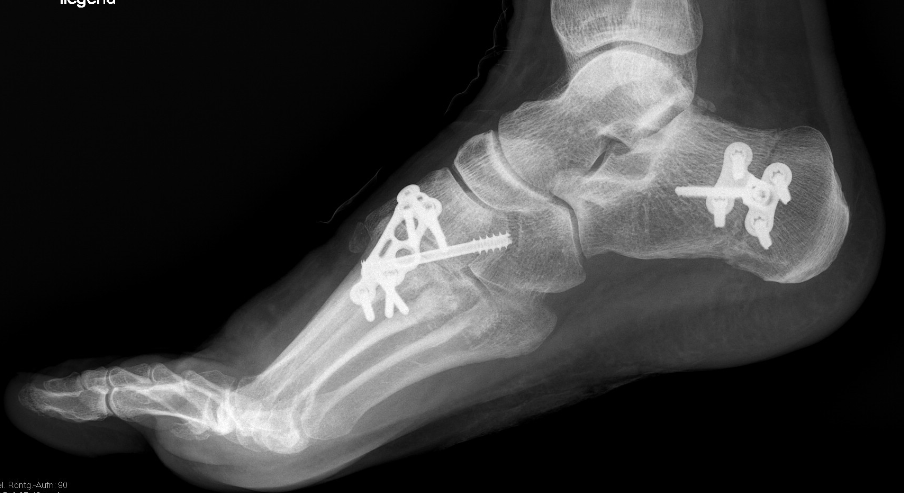

Gesamtes Spektrum der Fuß und Sprunggelenkchirurgie (Plattfuß, Spreizfuß, komplexe Vor-, Mittel- und Rückfußkorrektur, Krallenzehen und Hallux valgus/rigidus, Morton Neurinom)